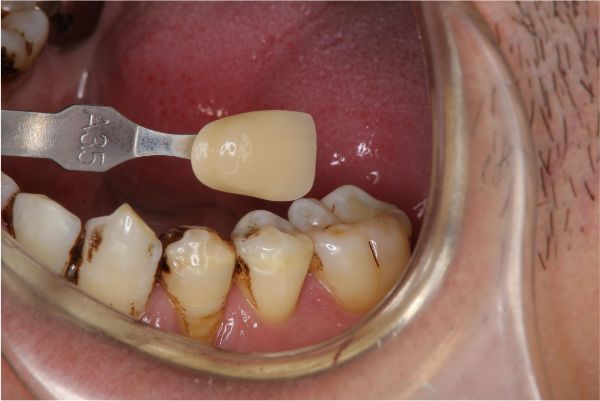

照相比色